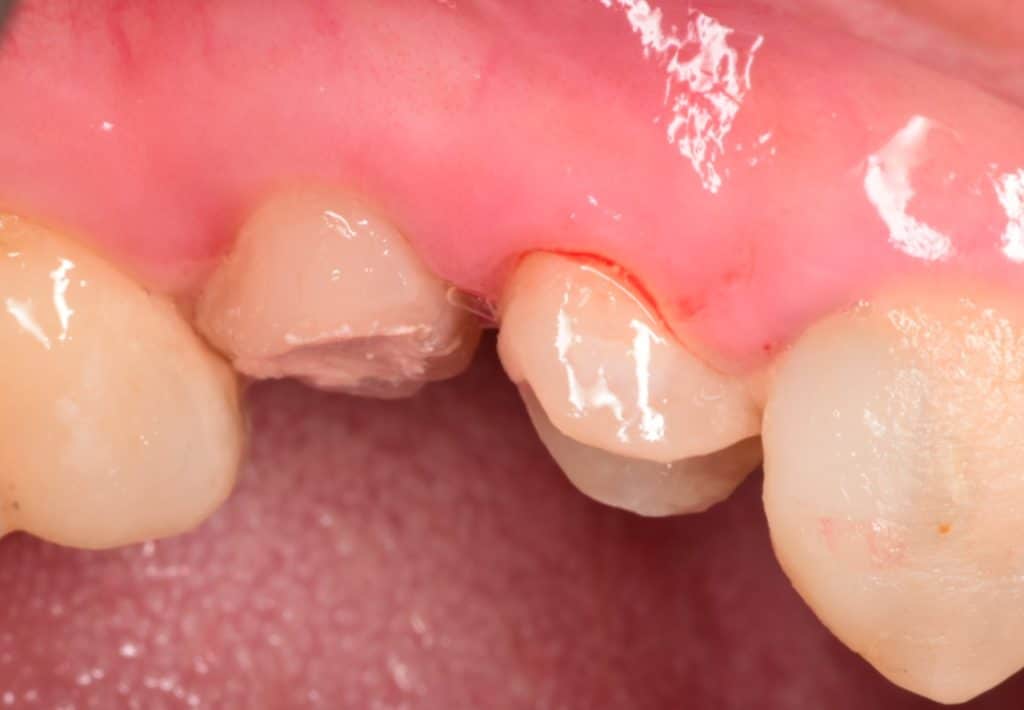

Buccal view showing the final cavity

Buccal view after composite building

Preparation done , macro-core buildup for premolars

Buccal view showing the macro-core buildup